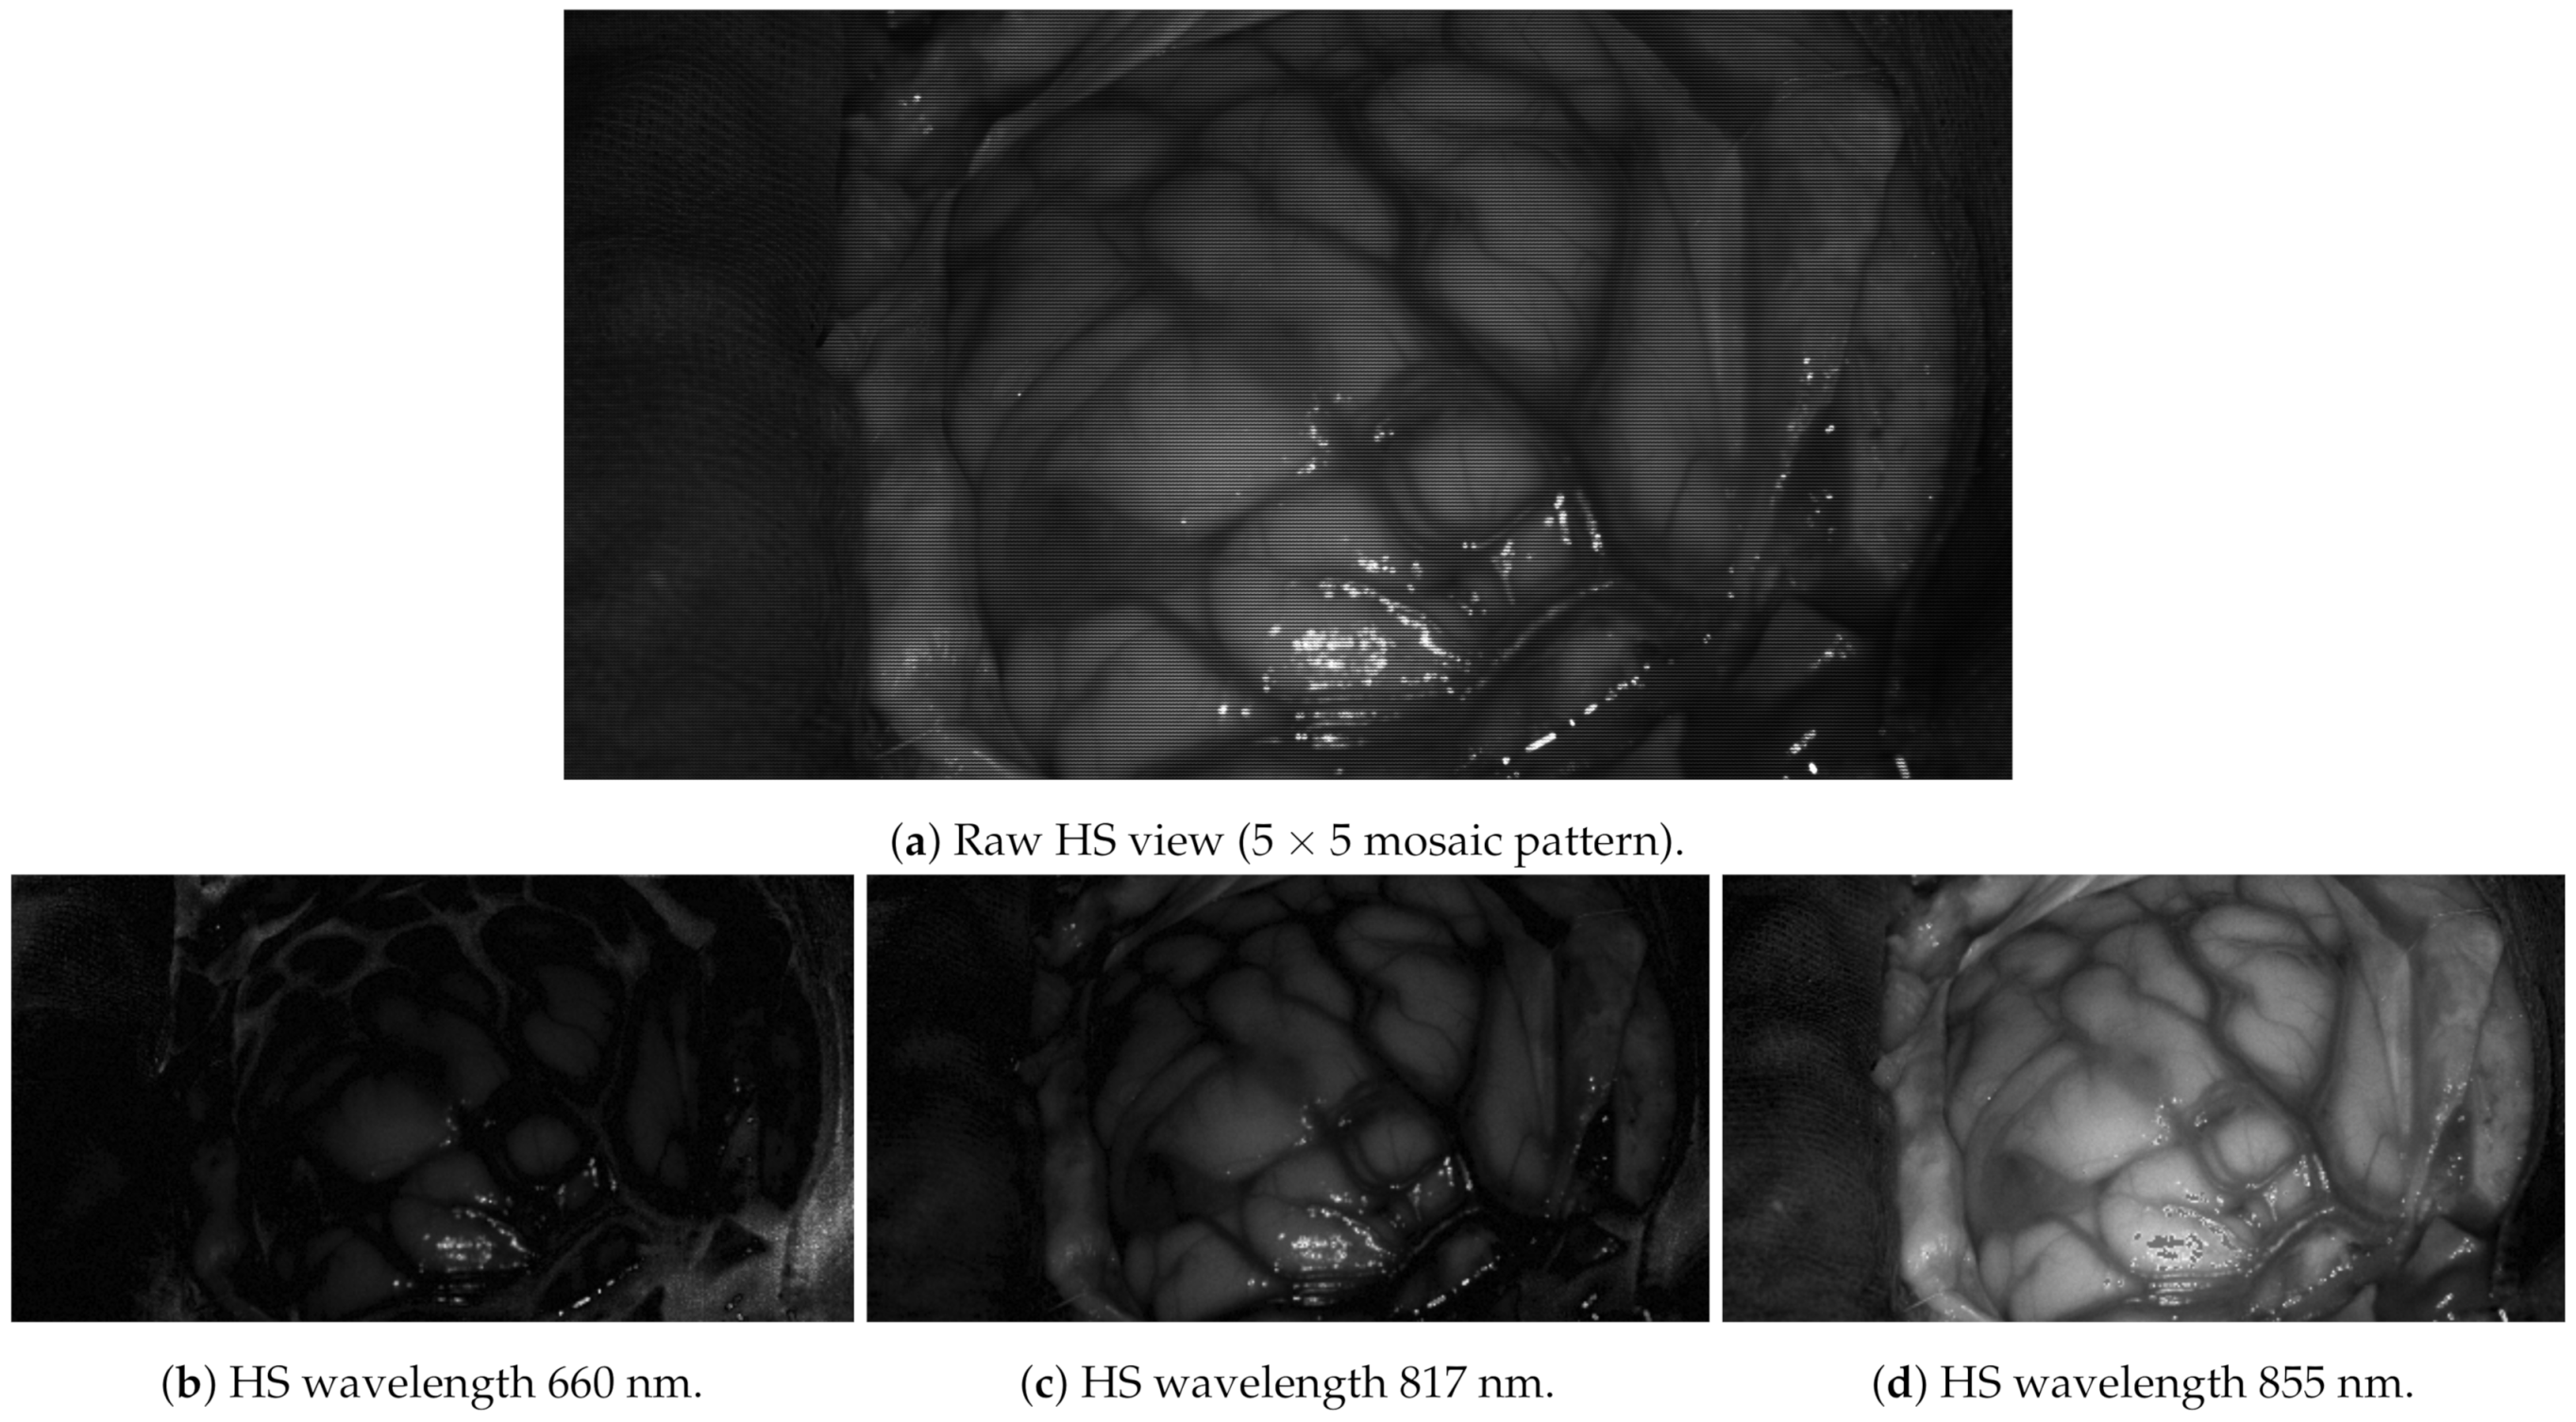

The multiview dataset was acquired in a laboratory using the same illumination conditions as the operating room and preprocessed to test GoRG. Preprocessing comprises radiometric calibration, cube generation, spectral correction, and interpolation at a factor of 2, leading to images. The dataset information is depicted in Table 2. It is important to notice the reduced depth range and depth steps, 60 cm and 100 steps, respectively; compared to the YUV sequences, this range is limited. This is designed to emulate functioning in the operating room. As an example, Figure 14 shows a real HS image captured during a surgical operation.

Figure 14.

Brain cancer operation HS image example. Only three of its 25 bands are represented.